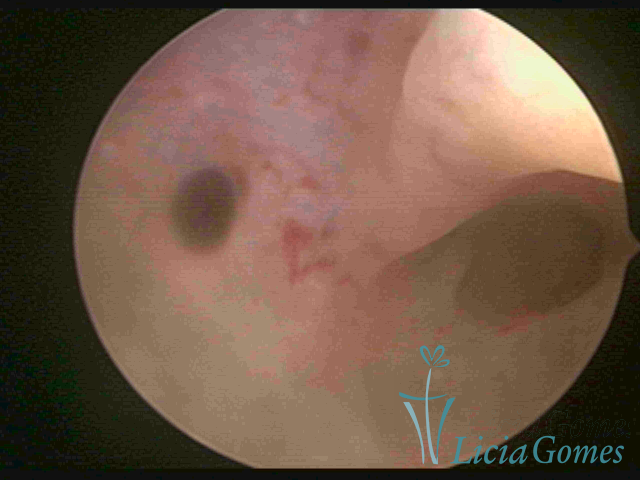

ADENOMYOSIS

The presence of endometrial tissue on the muscular layer of the uterus.

Video hysteroscopy allows diagnosing the lesions next to the superficial myometrial layers next to the endometrium, allowing the view of in situ, purplish, or chocolate brown lesions.